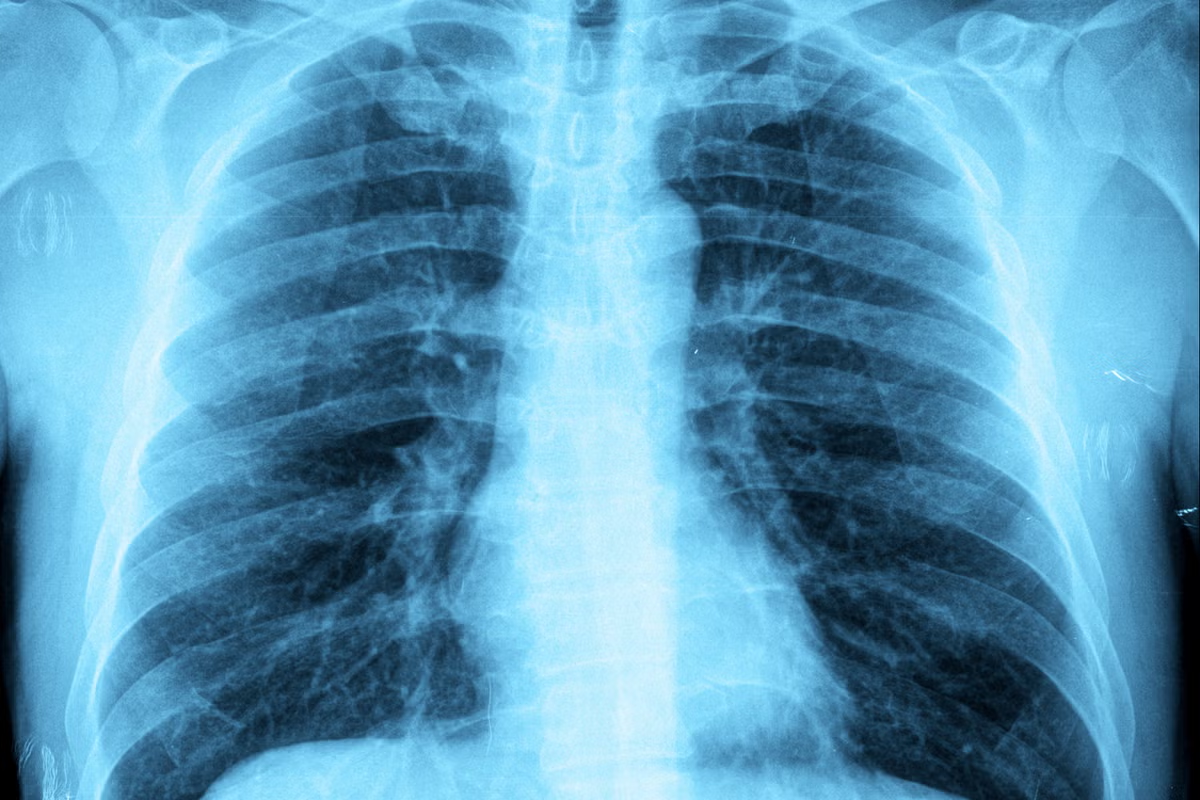

Tests like chest X-rays, blood tests, and lung function tests help tell bronchitis apart from these other conditions.

Chest X-ray |

Usually not required |

May be used to rule out other conditions |